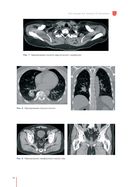

"Рекомендации по проведению стереотаксической лучевой терапии на аппарате "КиберНож" – это подробное руководство по вопросам необходимости применения стереотаксической лучевой терапии при различных злокачественных и доброкачественных процессах. Книга включает в себя детальное описание физико-технических особенностей роботизированной радиохирургической системы "КиберНож" и развернутые рекомендации по использованию аппарата для лечения различных онкопатологий и доброкачественных новообразований. Каждая глава снабжена клиническими примерами и планами лечения.